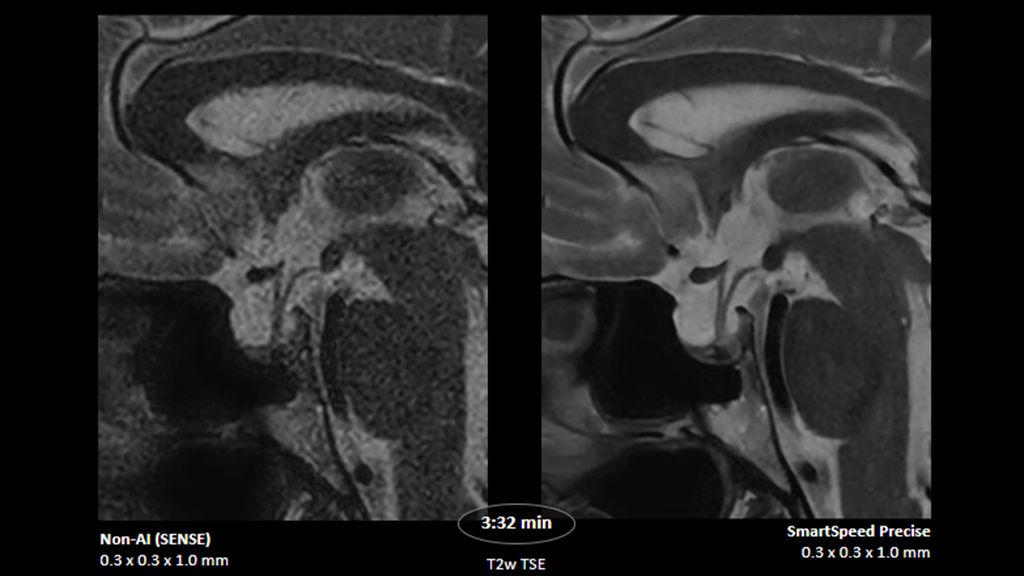

1. Compared to SENSE imaging, with no loss in image quality.

2. Reconstruction technology Compared to conventional (SENSE/ Compressed SENSE, SmartSpeed AI) imaging. Sharpness was evaluated with phantom scanning.